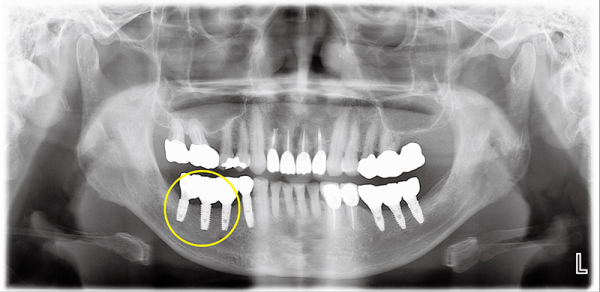

또한 이식된 뼈가 주변잇몸의 압력으로 인하여 흡수되는 것을 방지하기 위해 금속막을 이용하여 공간을 형성, 6개월 후 금속막을 제거한 후 새 임플란트를 식립했다.

다음 사진(그림2)은 임플란트 식립이 완성된 상태에서 촬영한 파노라마다.